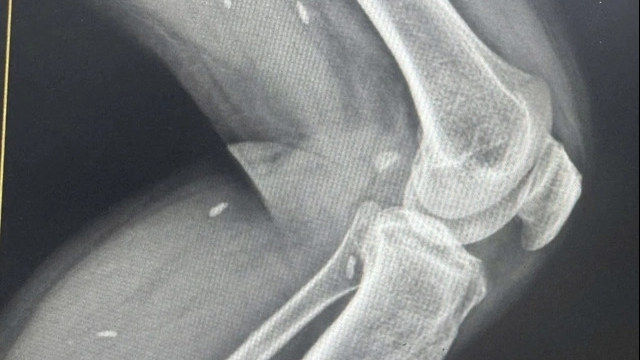

Cả 2 ca mổ được thực hiện bởi PGS.TS Phạm Anh Vũ cùng kíp phẫu thuật gây mê hồi sức tại Trung tâm điều trị theo yêu cầu và quốc tế của Bệnh viện Trung ương Huế. Sức khỏe các cháu diễn biến tốt, ra viện sau mổ 5 và 7 ngày.